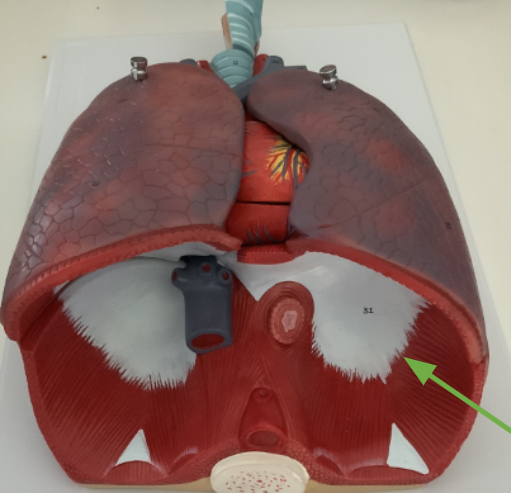

What structure is this?

Diaphragm